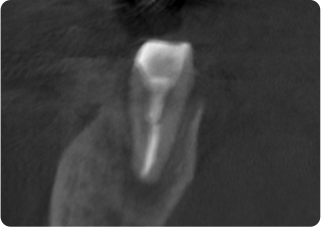

精密根管治療②

術前

術後

| 主訴 | 奥歯で噛むと痛い |

| 治療期間/回数 | 1ヵ月、3回 |

| 価格(税込) | 88,000円(税込) |

| リスク・副作用 | 病変再発、歯根破折の可能性 |

| ポイント | う蝕検知液を用い、むし歯の取り残しが無いようにし、ラバーダム防湿を行い、無菌的に根管治療を行った。根管充填材は、殺菌作用の強い保険適応外のMTAセメントを使用した。 |